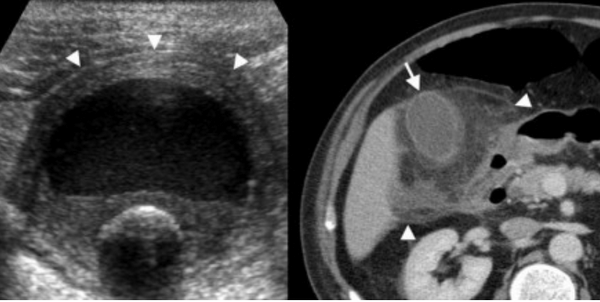

(Левый) На поперечном УЗ срезе у пациента с эмфиземой и перфорацией желчного пузыря определяется разрыв стенки, отмечается исчезновение эхогенной полосы слизистой. В просвете желчного пузыря определяются газ и скопление перипузырной жидкости.

(Правый) При КТ с контрастным усилением на аксиальной томограмме у этого же пациента наблюдаются признаки острого эмфизематозного холецистита с перфорацией. Виден фокальный разрыв стенки желчного пузыря. Также определяется газ в просвете пузыря и в перипузырном пространстве.